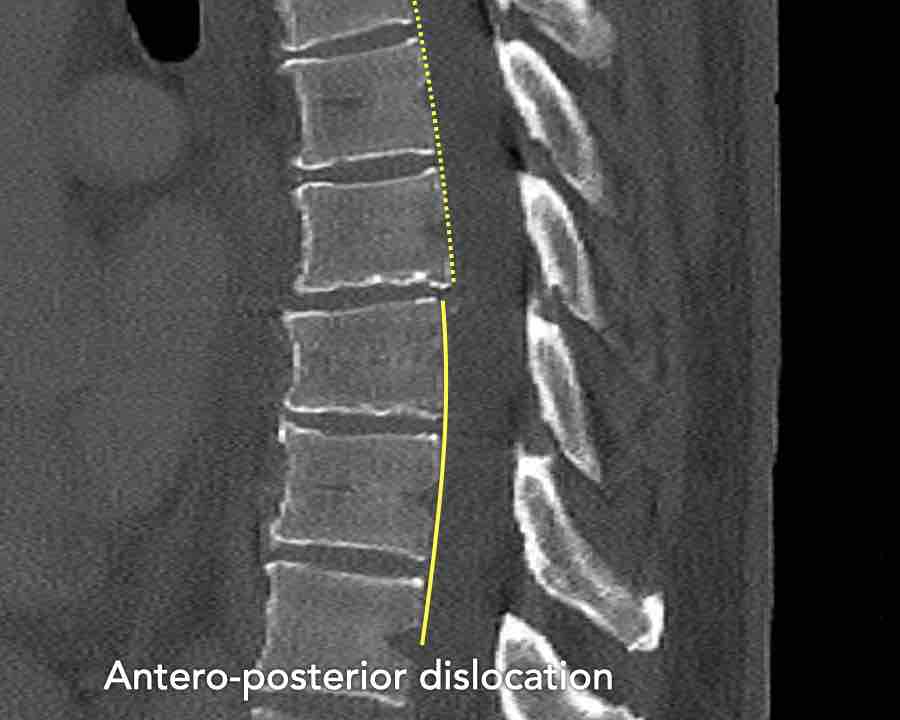

Findings

- Vertical fracture of the posterior border of the vertebral body. It looks a bit odd.

- Again we first have to look for the presence of a type C injury.

- Notice that there is a subtle posterior dislocation of the proximal levels. So this has to be C injury.

Conclusion

Injury type C + A3